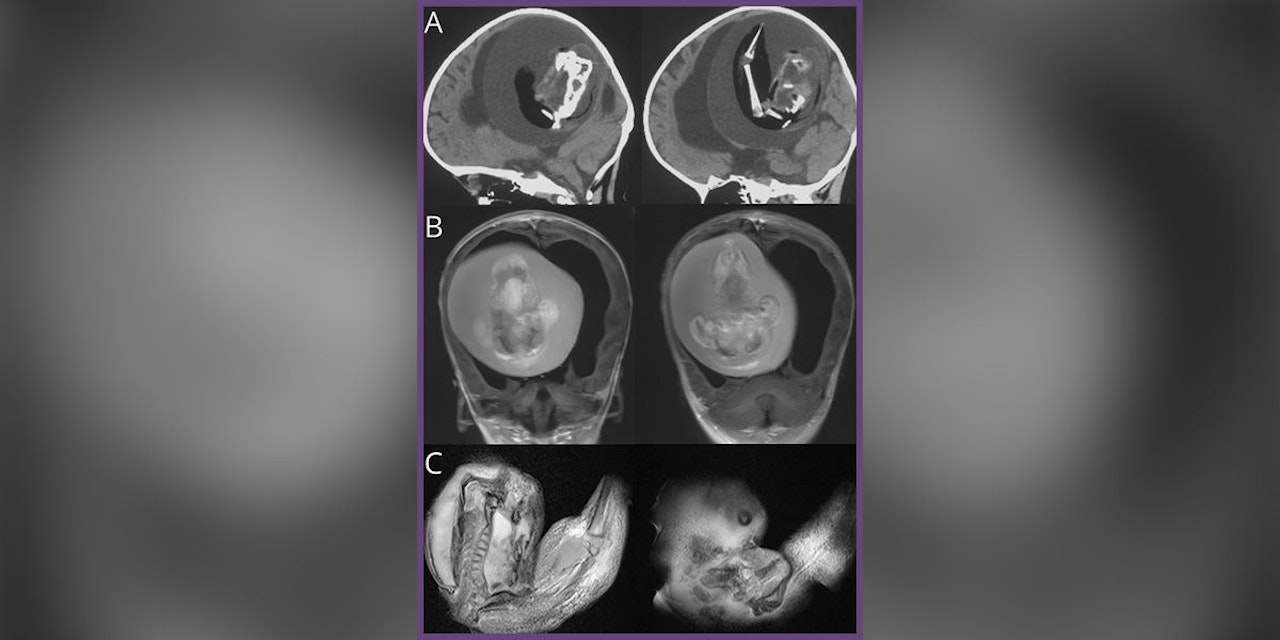

Der Fall wurde in der Zeitschrift Neurology der American Academy of Neurology veröffentlicht. Der Fetus in Fetu wurde erst entdeckt, als die Eltern ihre Tochter im Krankenhaus untersuchen ließen, weil sie einen vergrößerten Kopf und Probleme mit der Motorik hatte. CT-Scans zeigten, dass ihr ungeborenes Geschwisterchen gegen ihr Gehirn gedrückt wurde. Außerdem hatte sie einen Hydrocephalus ("Wasserkopf") – eine Flüssigkeitsansammlung tief im Gehirn, die einen vergrößerten Kopf, extreme Schläfrigkeit und Krampfanfälle verursachen kann. Die Ärzte konnten den Zwilling aus dem Kopf entfernen und erklärten, dass er obere Gliedmaßen, Knochen und sogar Fingernägel ausgebildet hatte, was bedeutet, dass er wahrscheinlich noch Monate nach der Geburt seines Geschwisters weiterwuchs. Ob das Mädchen Langzeitschäden davontragen wird, ist unklar.

Bilder des entfernten Fötus gibt es in unserer Bildergalerie. Ansehen auf eigene Verantwortung!